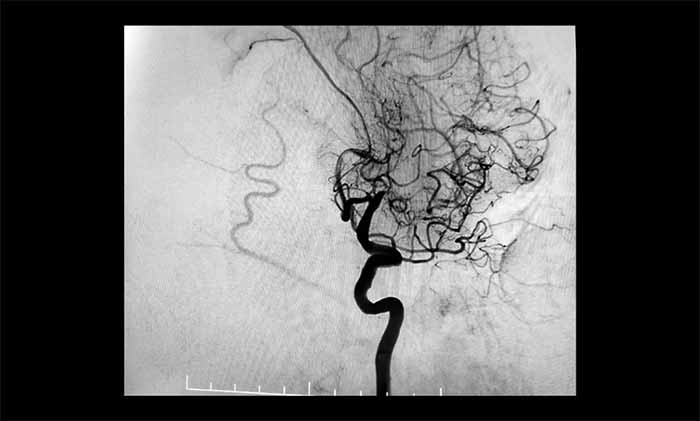

近日,一位70多歲患者因反復(fù)出現(xiàn)右側(cè)肢體無力、言語含糊、口角流涎,被診斷為左側(cè)大腦中動(dòng)脈完全閉塞。他還合并頸內(nèi)動(dòng)脈動(dòng)脈瘤、椎動(dòng)脈狹窄等復(fù)雜問題,手術(shù)難度極高。其中,左側(cè)大腦中動(dòng)脈M1段的慢性完全性閉塞,是導(dǎo)致其神經(jīng)功能缺損反復(fù)加重的主要原因。

席剛明教授、王貴平博士團(tuán)隊(duì)經(jīng)過全面評(píng)估,最終在全麻下精細(xì)操作,利用微導(dǎo)絲穿過閉塞段,并以“球囊擴(kuò)張+支架置入”完成血管再通,為患者打通這條關(guān)鍵的“生命線”。術(shù)后患者血流通暢,恢復(fù)良好。

▲ 左側(cè)大腦中動(dòng)脈完全閉塞